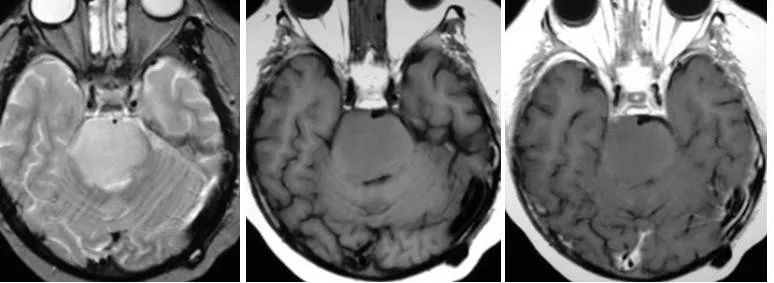

横断位T2WI及FLAIR示脑桥高信号肿块,横断位及矢状位T1WI C示一膨胀性肿块累及脑桥并向中脑和延髓延伸,增强未见强化。

浸润性脑干星形细胞瘤:星形细胞瘤通常位于脑的某些区域,在成人,浸润型星形细胞瘤通常位于大脑半球(75%),在儿童,浸润型星形细胞瘤通常位于脑干,毛细胞型星形细胞瘤通常位于小脑。浸润性星形细胞瘤通常侵犯脑干,但导致其损害,它可以发生恶性转化。